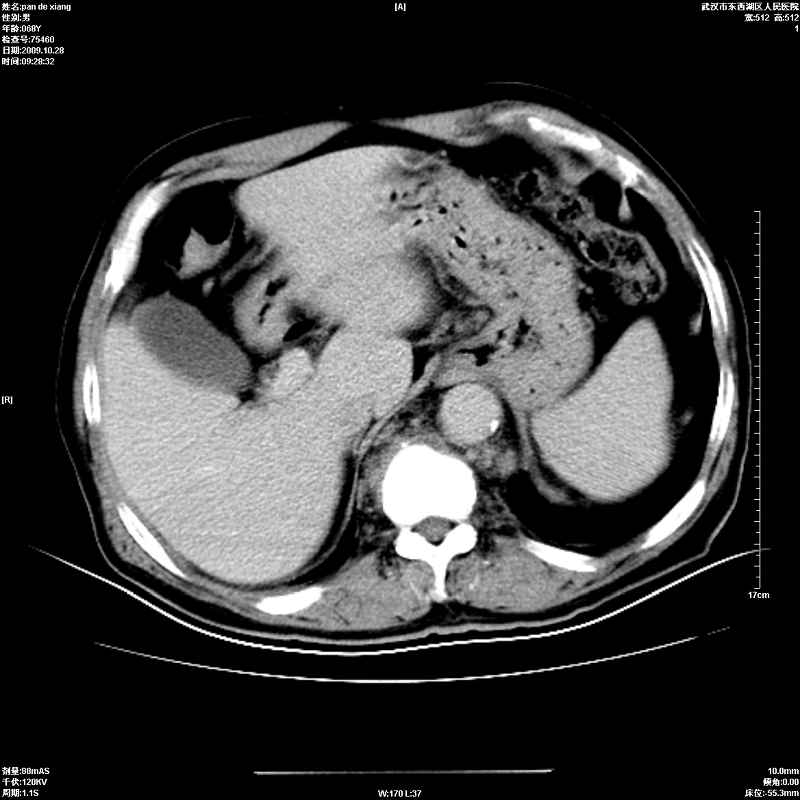

以下是引用杀毒软件在2009-10-28 20:41:00的发言:[br]结合临床考虑---白血病双肾改变或淋巴瘤。

以下是引用zxl51642在2009-10-29 9:59:00的发言:[br]结合临床“单克隆免疫球蛋白血症”,考虑双肾为继发损害并肾功能不全(尿中大量igg及少量iga、igm等大分子免疫球蛋白滤出所致继发损害),椎前软组织肿块为髓外造血。与浆细胞瘤有区别,平扫时有战友说的很清楚。